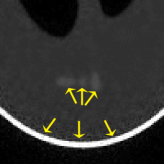

where J1subscript𝐽1J_{1} is the first kind Bessel’s function of order 111. Then using the variable density random sampling method in [46], we generate 20%percent2020\% undersampled k-space data. The complex white Gaussian noise is also added so that the resulting SNR of the samples is approximately 25dB25dB25\mathrm{dB} (See Fig. 3).

Refer to caption

(a) Fully sampled

(b) Ground truth

(c) Sample mask

(d) Undersampled

Figure 3: Dataset for the phantom experiments. Fully sampled k-space data, its inverse DFT as a ground truth, the undersampling mask, and the undersampled k-space data.